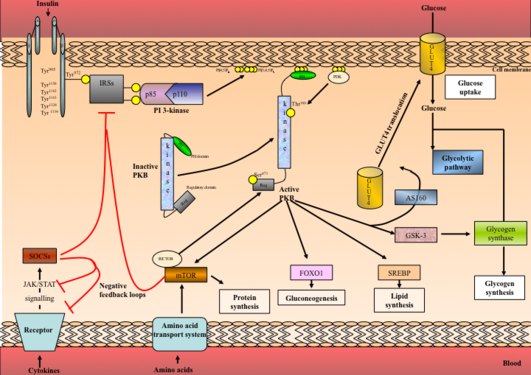

Proteomstudier innebærer studier av proteinuttrykket i et system (celle, vevsprøve, organ) under forskjellige betingelser og situasjoner. I toksikologisk sammenheng kan dette gi viktig informasjon om virkningsmekanismer for toksikologiske prosesser, samtidig som det kan gi verktøy for å måle eller følge en toksikologisk respons i form av proteom-”fingeravtrykk” og påvisning av nye biomarkører.

I våre studier jobber vi både med å utvikle nye verktøy for å kunne påvise miljøgifter på et tidlig stadium, og med å forstå mekanismene som ligger til grunn for forskjellige typer effekt, f.eks. gjennom reseptoraktivering og biotransformasjon.